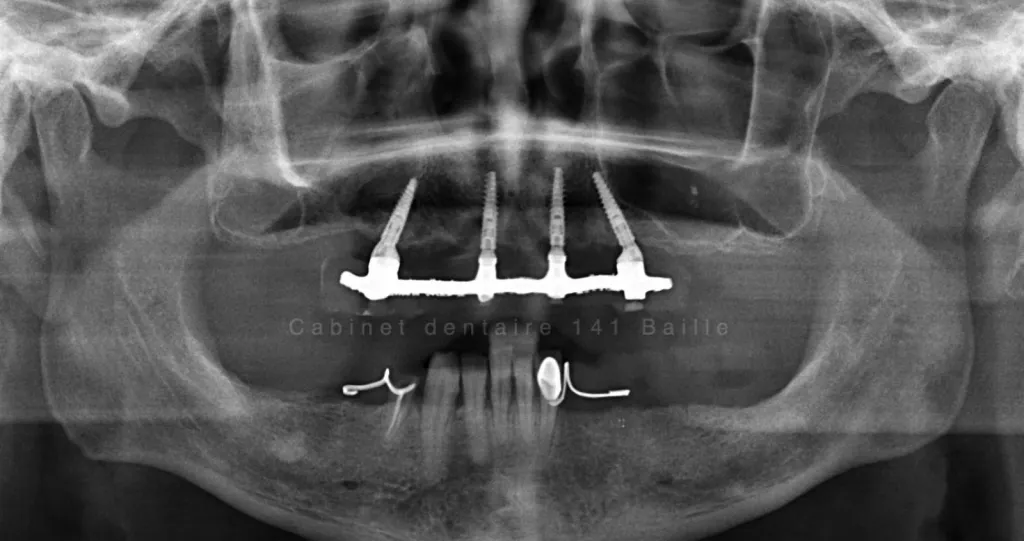

L'implant dentaire est une sorte de cheville que le chirurgien dentiste implantologue place dans l'os alvéolaire.

La tenue de l'implant est conditionnée par des facteurs de biomécanique ,qui dépendent essentiellement de la qualité de l'os et de sa quantité sur le site receveur de l'implant.En cas de manque de volume osseux ,il sera impossible sans réaliser de greffe osseuse dentaire préalablement à la pose de l'implant d'envisager ce type de technique.

On parle alors de Régénération Osseuse Guidée (ROG).Ces techniques de chirurgie avancée pré-implantaire ont énormément évolué et permettent aujourd'hui d'étendre les possibilité du traitement par implant dentaire aux patients ayant eu une forte perte d'os.

Le principe est de créer  un volume d'os plus important par des techniques de coffrage et d'isolation par des membranes spécifiques qui permettent à l'os alvéolaire de se différencier sans être envahi par les cellules de la gencive.

On est dans des techniques de chirurgie osseuse avancées qui nécessitent un environnement stérile et des compétences particulière de la part du chirurgien implantologue.